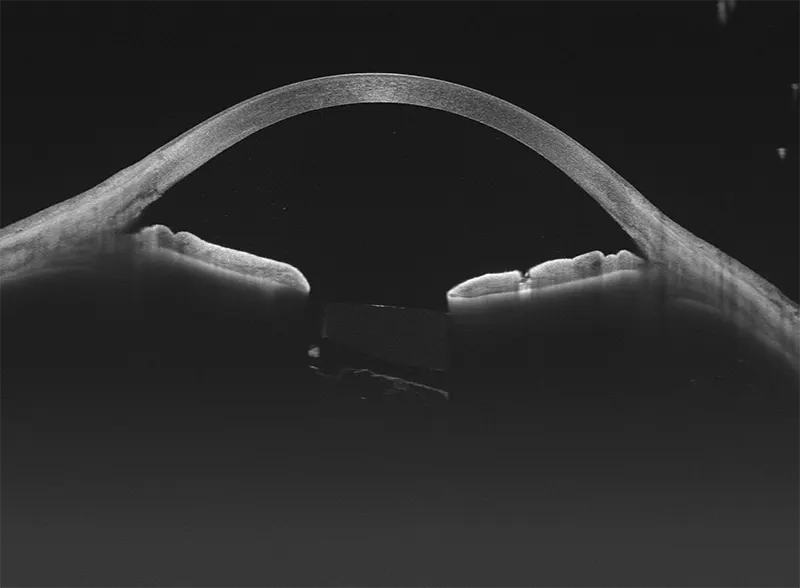

Galería OCTs del TowardPi Yalkaid